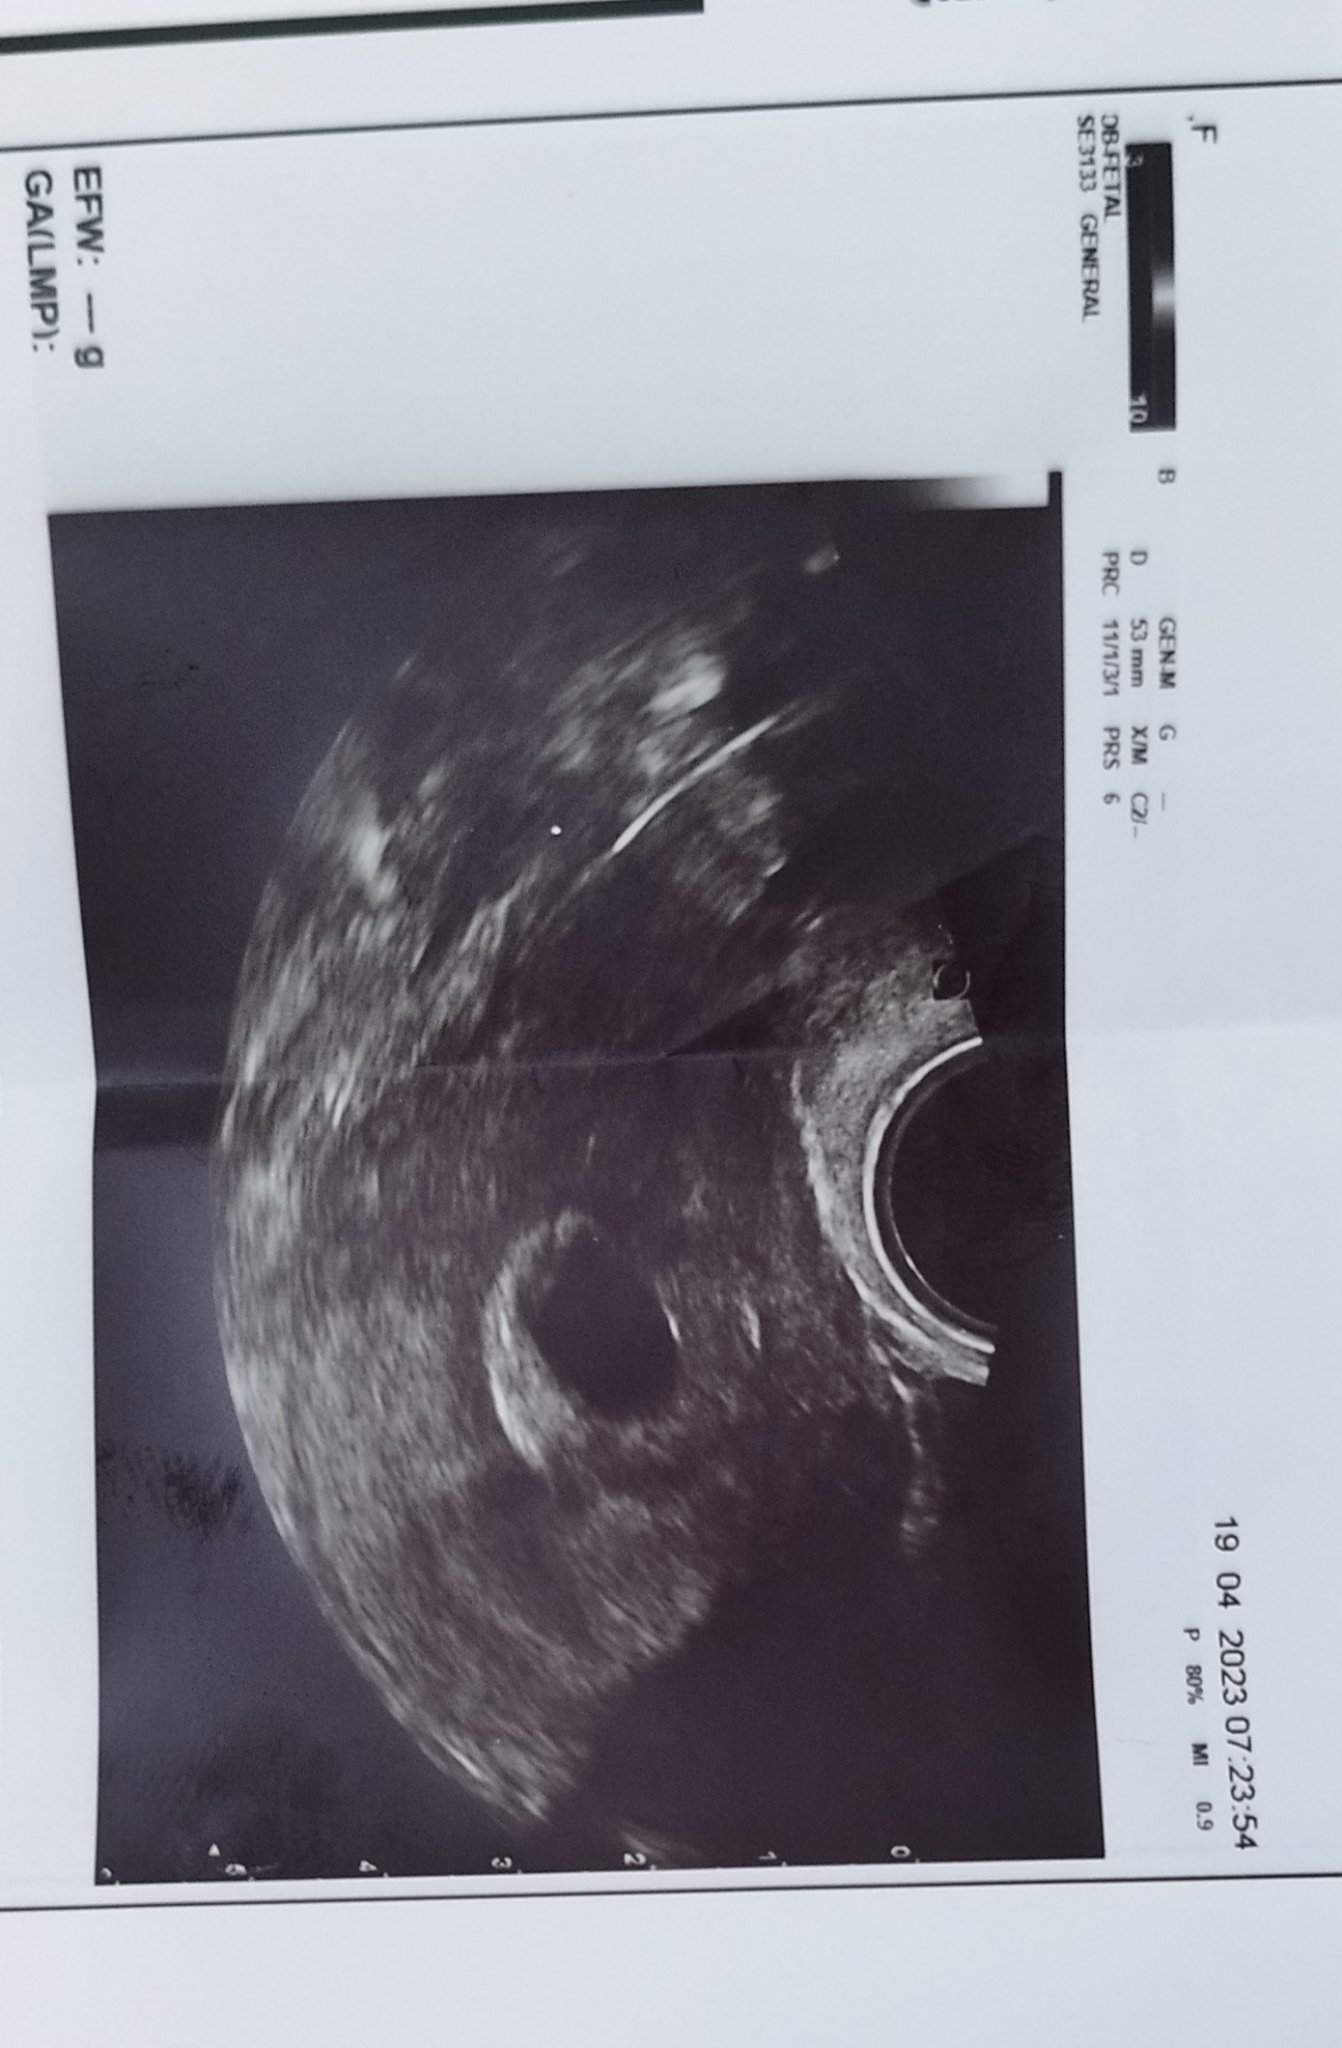

Здравейте и от мен! Накратко ще се опитам да разкажа какво се случва и при мен и ще се радвам на отзовали се, тъй като вече и аз не знам какво да правя, да търся ли други лекари, по-добри апаратури и тн. На 23 март разбрах, че съм бременна, на 12 април след леко прокървяване, лекарят ми каза, че това е кухо яйце, ембрион не се вижда, плоден сак и жълтъчно мехурче - да, но ембрион няма и шанс да се види също няма и трябва да се направи кюртаж. Посетих и второ мнение и там шанс никакъв не ми се даде. Не питайте как приех новината... Тежко.. това ми е първа бременност. Миналата седмица отидох при втория специалист подготвена да изберем дата за кюретаж. Да, обаче докторът ми каза, че плодният сак се е увеличил и е добре да изчакаме до утре. Шансът вече беше 50 на 50. Прикачвам ви и снимката от последния преглед, на която виждам много малка бледа точка вляво, но вече губя надежда. Утре е прегледът ми и съм подготвена за най-лошото. Виждате ли нещо на тази снимка, как ви се струва размера 53 мм., Би трябвало да съм в 7 г. с.